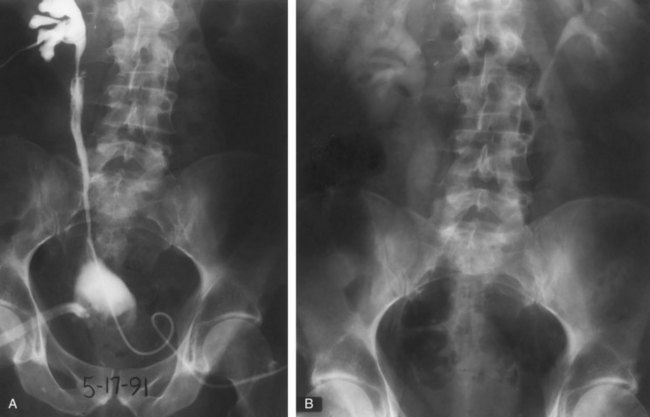

Open conservative surgery may be applied in selected cases when nephron sparing for preservation of renal function is required (Gittes, 1966, 1980; Petkovic, 1972a, 1972b; Mazeman, 1976; Johnson and Babaian, 1979; Babaian and Johnson, 1980; Cummings, 1980; Wallace et al, 1981; Tomera et al, 1982; McCarron et al, 1983; Zincke and Neves, 1984; Bazeed et al, 1986; Ziegelbaum et al, 1987; Messing and Catalona, 1998). Tumor in a solitary kidney, synchronous bilateral tumors, and predisposition to form multiple recurrences, as in endemic Balkan nephropathy, are all reasons to consider nephron sparing (Fig. 53–6). Pyeloscopy as an initial diagnostic component to open conservative surgery has been supplanted by retrograde or percutaneous antegrade renal endoscopy (Huffman et al, 1985). Direct endoscopic visualization of the lesion and biopsy with cup forceps or brush establish a definitive diagnosis and tumor grade (Gill et al, 1973). The brush biopsy has renewed value because tissue obtained by small cup biopsy forceps used through narrow-caliber flexible endoscopes is limited. Preoperative determination of the stage of renal pelvis tumors remains difficult. Large size, broad base, and nonpapillary pattern favor tumor invasiveness. These improvements in initial diagnosis and assessment of tumor stage and grade allow more specific treatment, including conservative surgery when it is indicated.

Figure 53–6 Patient with an invasive tumor of the upper calyx of a solitary kidney. The patient elected an upper pole partial nephrectomy.